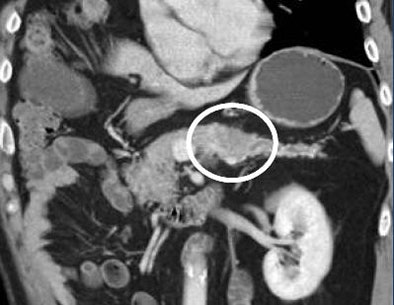

![]() |

| A splenic artery aneurysm mimics an islet cell tumor. |

"It's very easy to make mistakes, particularly by the head of the pancreas and the tail of the pancreas," he said. For example, a splenic artery aneurysm can easily be misdiagnosed as an islet cell tumor or a splenule, he said.

"Splenic lesions very much at times simulate pancreatic masses; it's a very difficult area," Fishman said. You have to look at arterial and venous phase enhancement, he said. One clue is that enhancement of the splenic artery is significantly matched with that of the spleen.

Findings involving the splenic artery, particularly if the artery is very tortuous, can easily simulate distal pancreatic lesions, Fishman said.